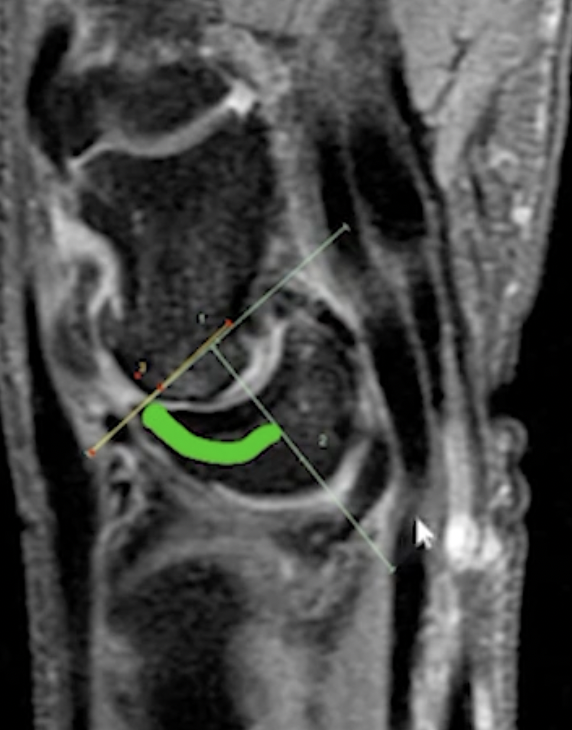

Scapholunate Advanced Collapse (SLAC wrist)

• High risk of developing DISSI - dorsal intercalated segmental instability

• Causes

• Scaphoid fracture = bony DISSI

• Distal radius fracture = compensatory DISSI

• Radius malunion = adaptive DISSI

• Dissociation of scaphoid and lunate = ligamentous DISSI

• Results in a lunate basically angulated volarly

• Look at angle below with green curved line

• Should be less than 60 deg, if >70 deg almost always DISSI

• Findings

• Hypertrophy of the radial styloid (scaphoid rubs against it) - stage 1

• Arthritis (joint space narrowing, degen of scaphoid) at scaphoradial joint - stage 2

• Narrowing, erosions of capito-lunate articulation - stage 3

• Generalized degeneration of the intercarpal and carpal-radial articulations - stage 4